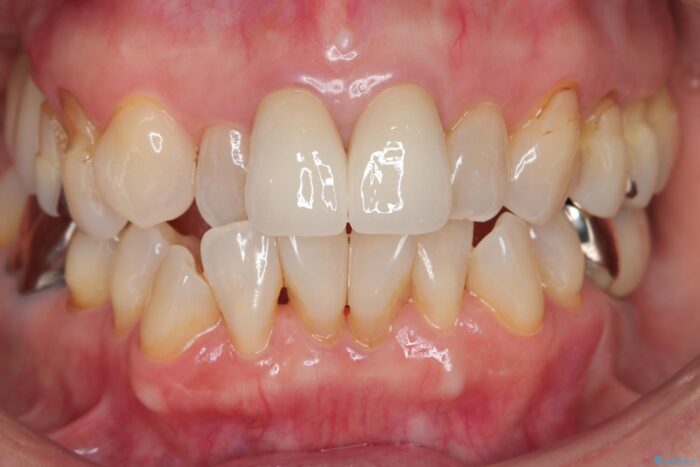

前歯の差し歯(クラウン)が黒ずんでいるとご相談にいらっしゃった患者様です。

黒ずみもなくなり、自然な色味で大変ご満足いただけました。